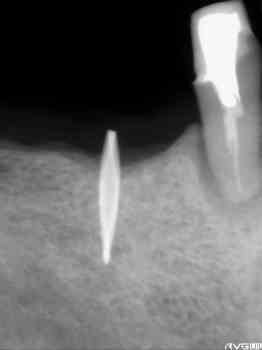

パノラマ写真